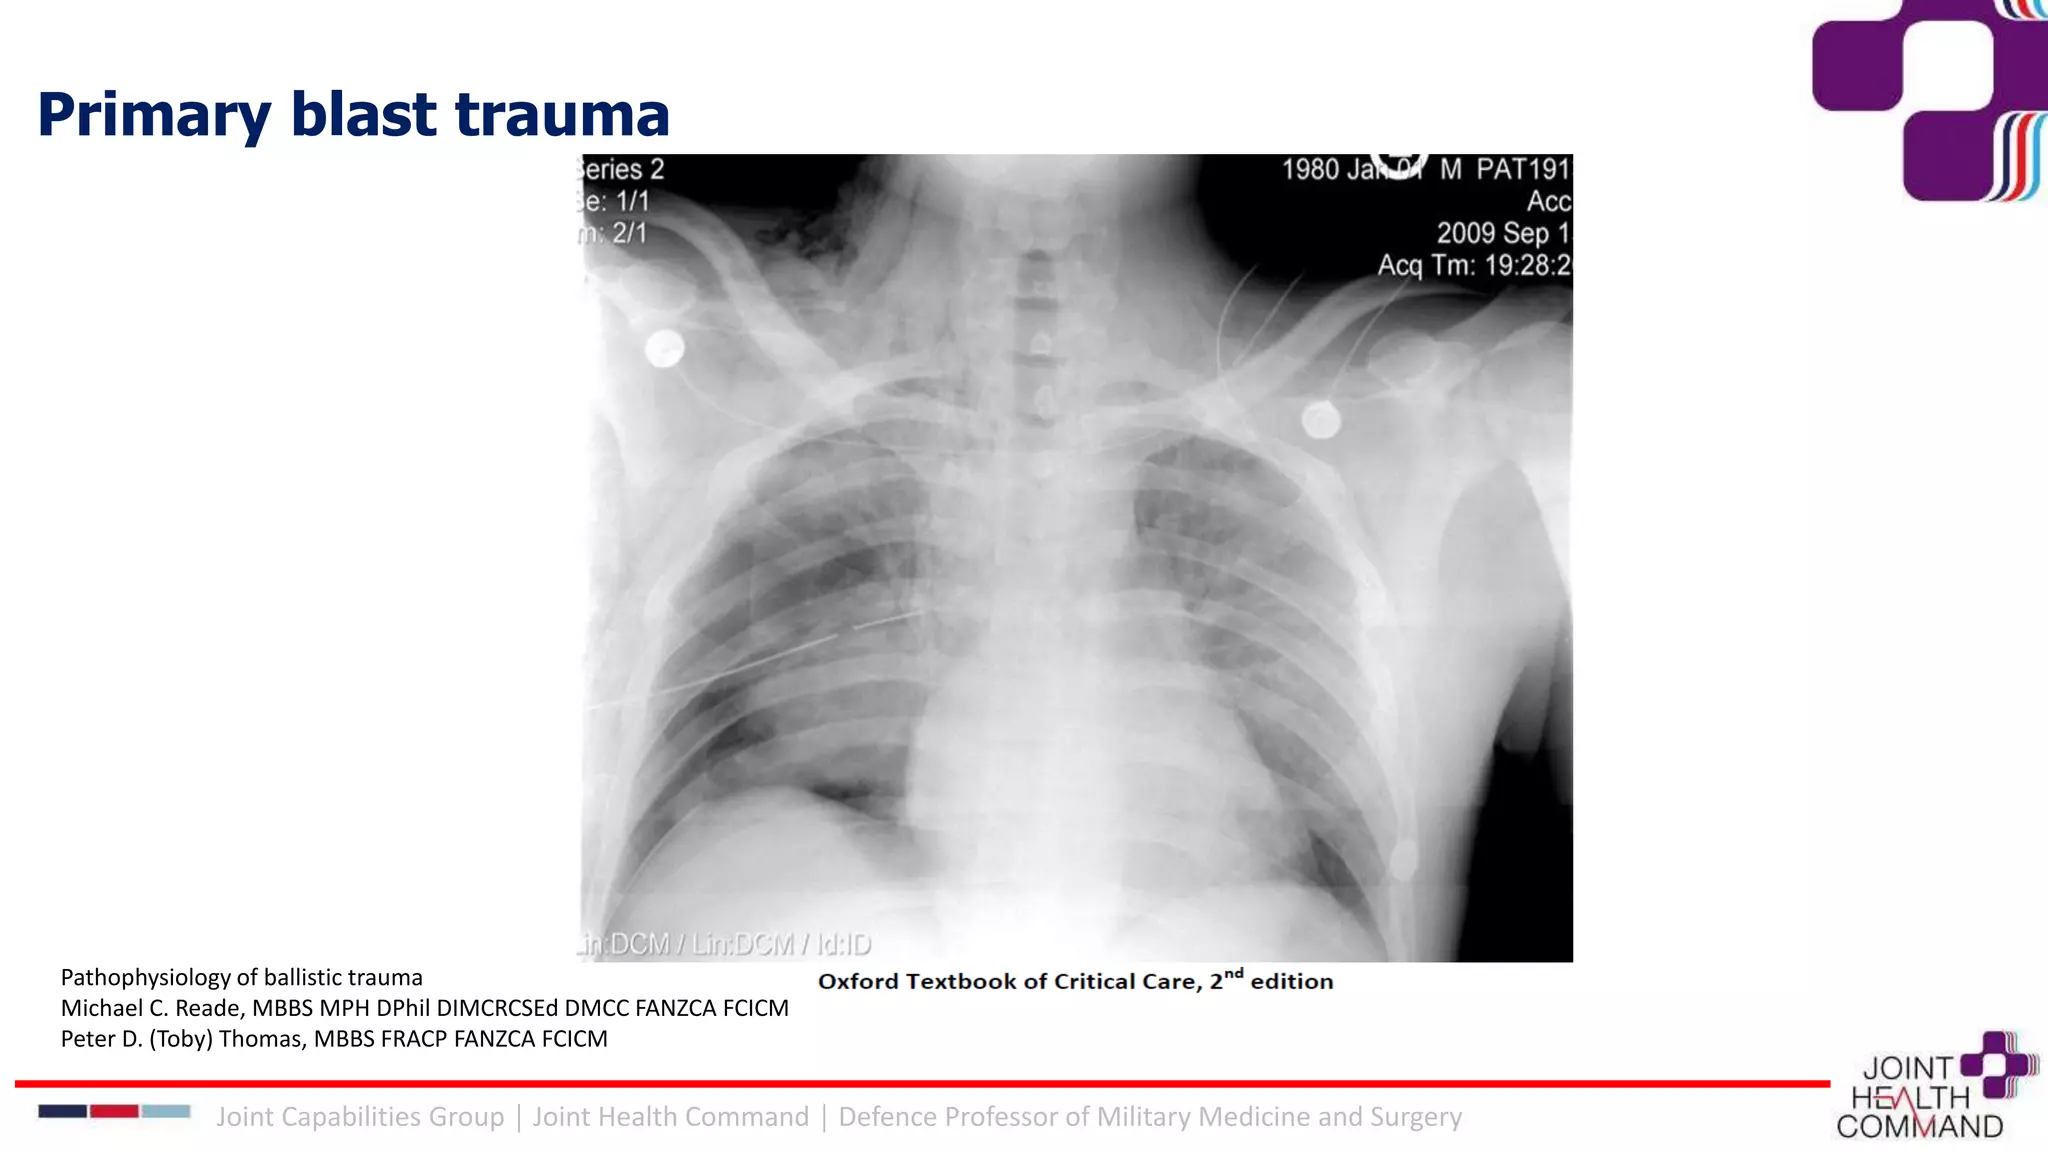

Primary blast trauma

Mechanisms of tissue damage by a blast wave:

• Spalling: as the wave moves from a more to less dense medium, disrupting the interface

• Implosion: due to compression then expansion of gas in hollow organs

• Shearing: blast wave causes different density tissues to accelerate at different speeds

Blast lung

• Pathogenesis: disruption of capillaries. Early deaths are due to arterial air emboli

(causing stroke and cardiac ischaemia).

• Develops over 24-72hrs and takes 7-10 days to resolve.

• Signs: hypoxaemia, frothy sputum, subcutaneous emphysema

• DDx pneumothorax, haemothorax, inhalation of toxic gases

Treatment: we have no idea!

• Extrapolate from ARDS principles (permissive hypercapnia, low tidal volume,

restrict fluid)

• Higher Ppeak = greater risk of air embolus (???)